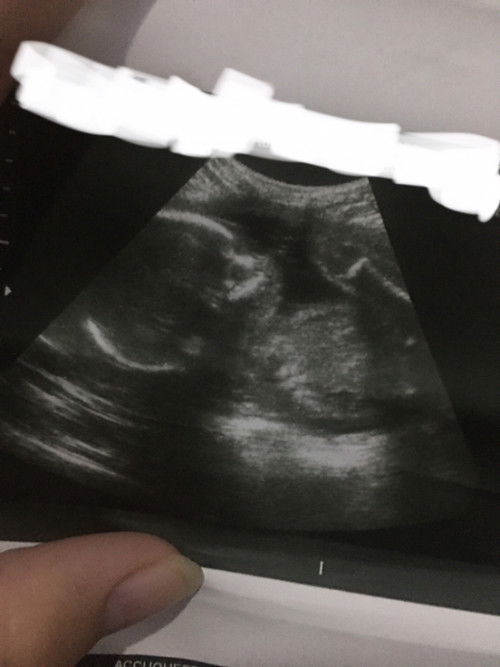

Kinakabahan kasi ako sa face ng baby ko dito sa ultrasound😔 diko alam kung may problem or what natatakot po talaga ako😔 mag aanim na buwan napo kasi nung nalaman kong buntis pala ako😔 may mga unhealthy habits po kasi ako nung mga panahon na hindi kopa alam na buntis na pala ako like (paginom,sigarilyo(minsan)😔 ano po sa tingin nyo based sa ultrasounds pics kinakabahan po talaga ako😔🙏🏻

did you ask your OB about sa interpretation ng ultrasound? may papel yan kasama momsh... dun nkalagay findings

CAS ka . hindi sapat yang isa o dalawang picture ng ultrasound mo para masabi na walang problema si baby mo

Pa CAS ultrasound ka po para mapanatag loob mo. Dun ichecheck yung organs ni baby